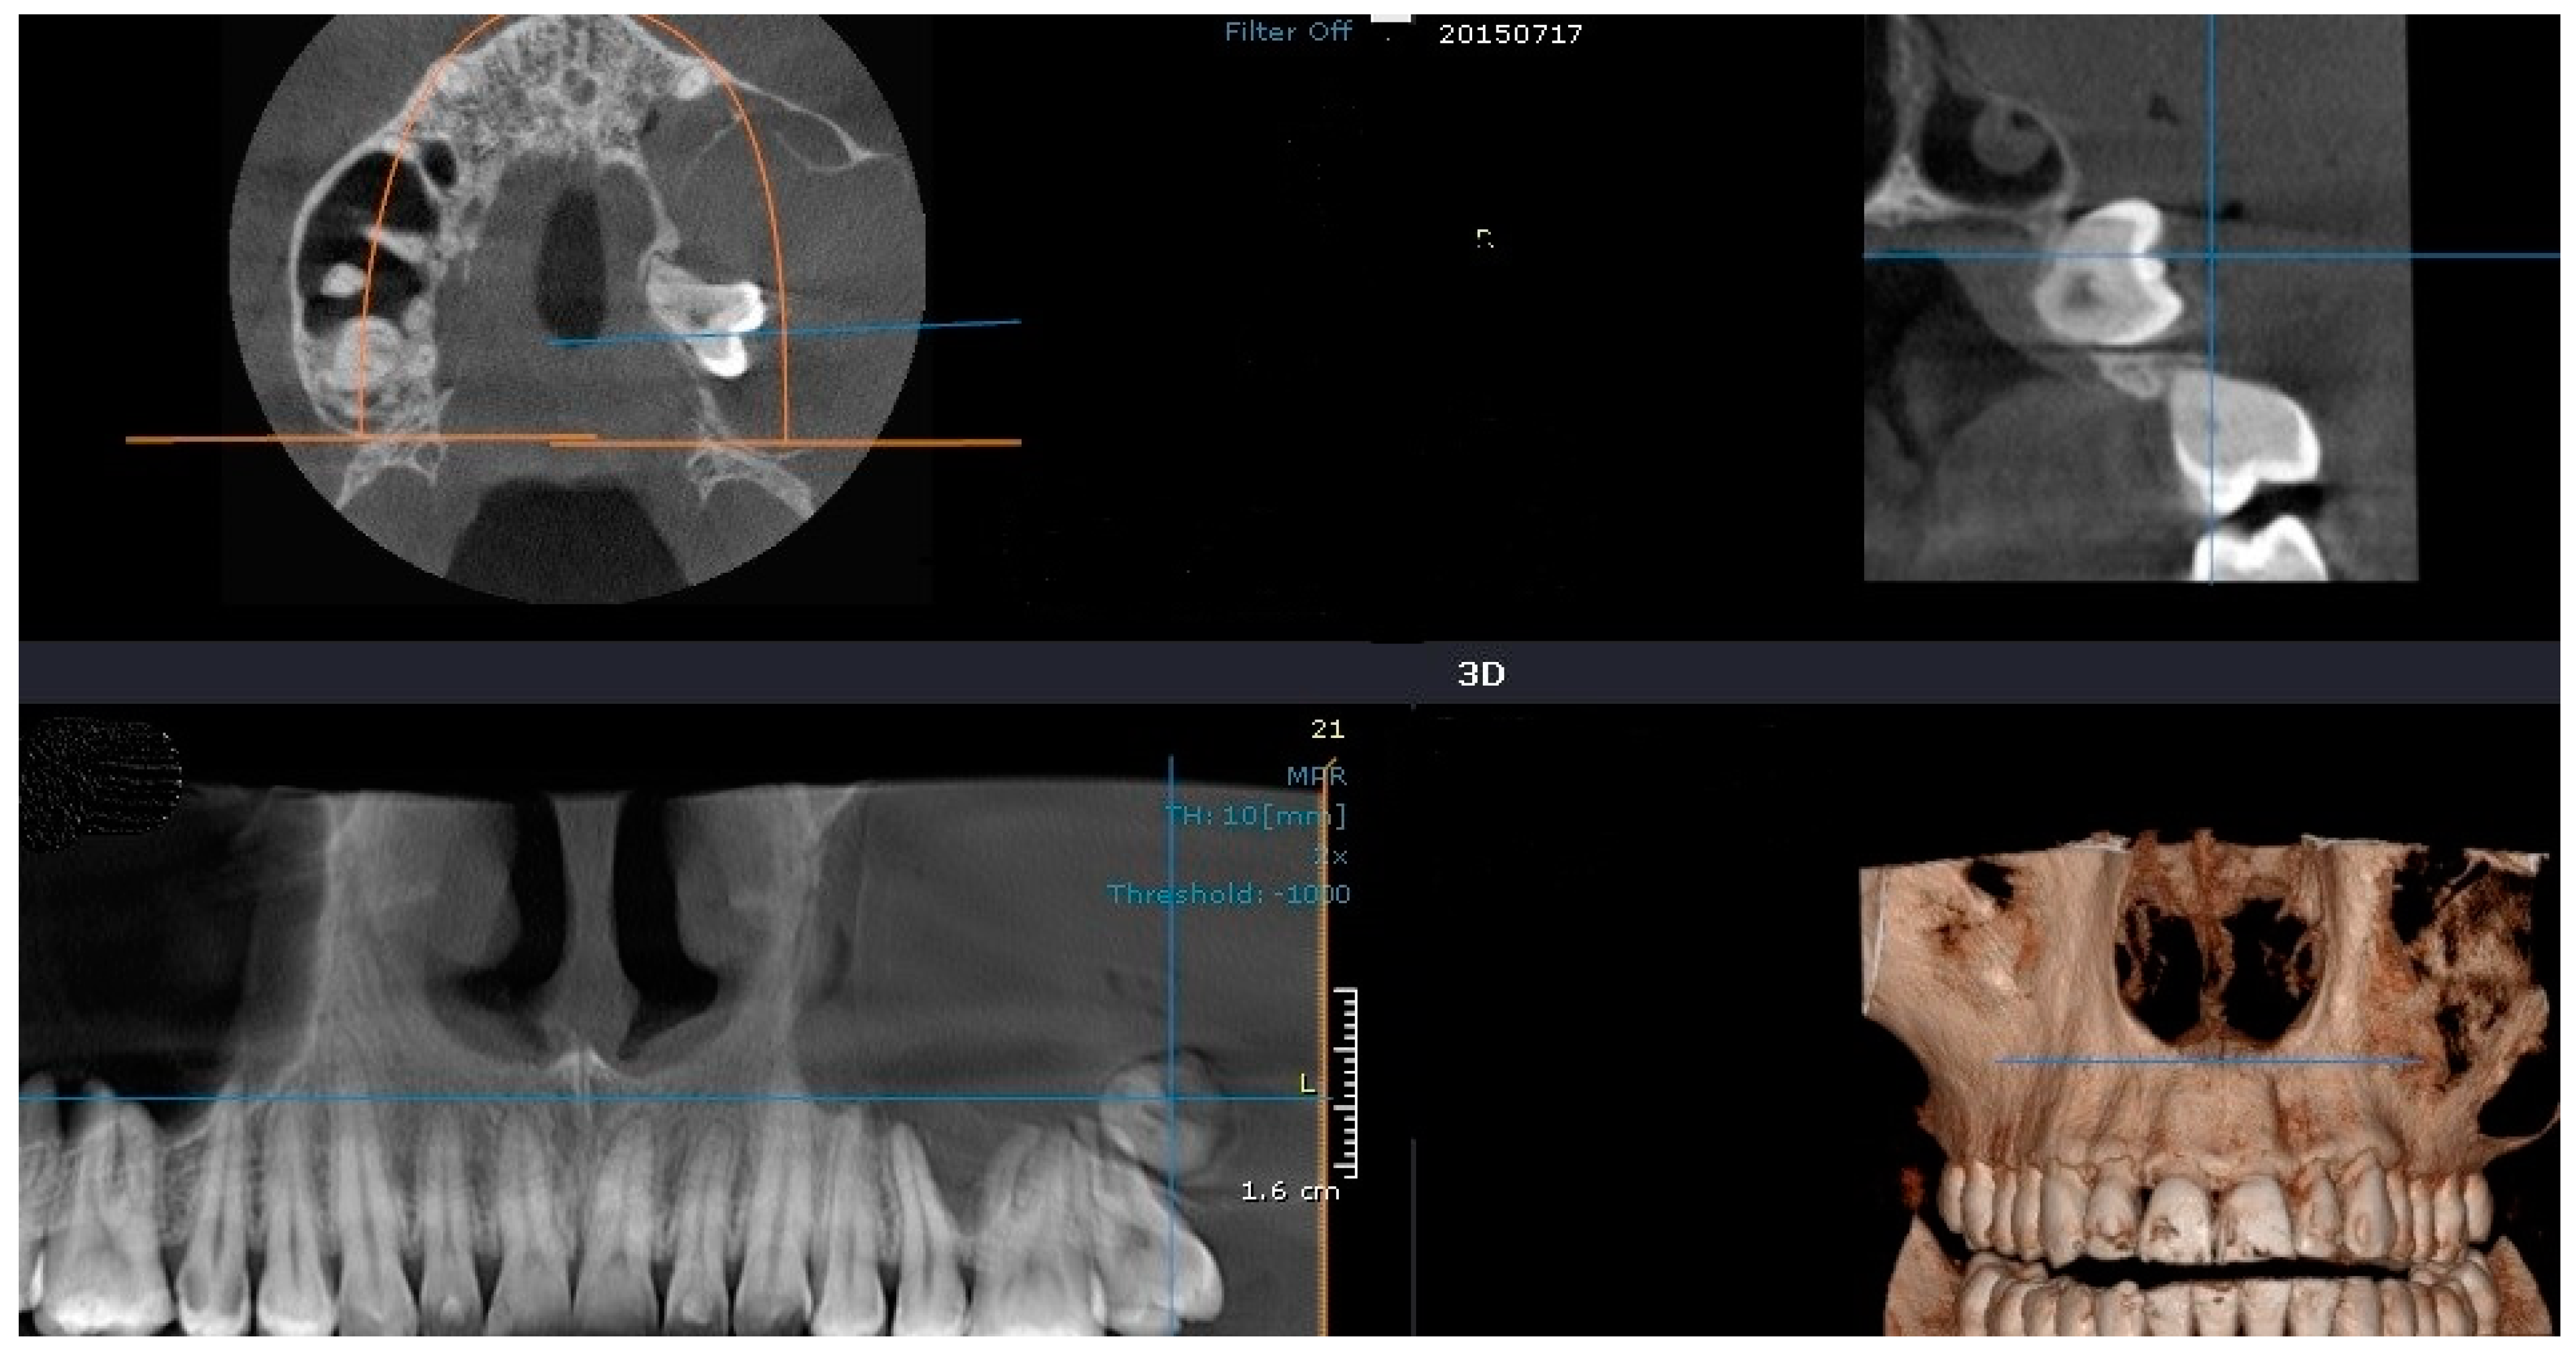

2.2.1. Case 1

2.2.2. Case 2

2.2.3. Case 3